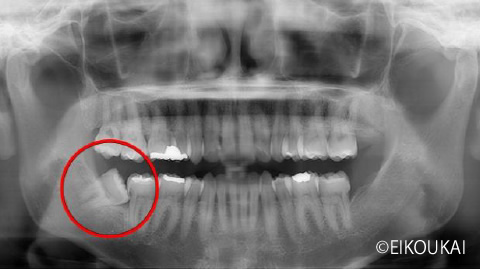

親知らずの虫歯トラブルをスピード解消。CT診断に基づいた安全な抜歯症例

治療内容 汚れが溜まり、虫歯があり右下の親知らずを抜歯しました。 金額 埋伏抜歯5,120円 CT 4,400円 治療期間 1日 通院回数 1回 リスク/副作用 抜歯後にしびれが出ることや、まれに腫れや痛みが長引くことがあります。

| 治療内容 | 汚れが溜まり、虫歯があり右下の親知らずを抜歯しました。 |

| 金額 | 埋伏抜歯5,120円 CT 4,400円 |

| リスク/副作用 | 抜歯後にしびれが出ることや、まれに腫れや痛みが長引くことがあります。 |